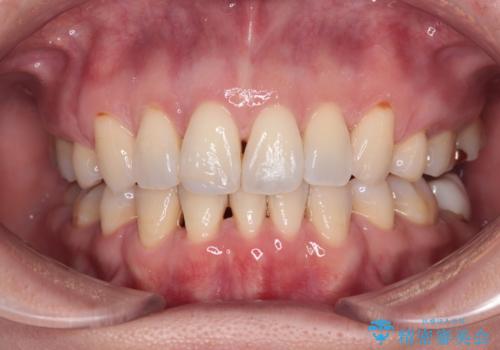

- 口元の突出感を改善したい。審美装置による抜歯矯正- 担当医 齋藤佑磨